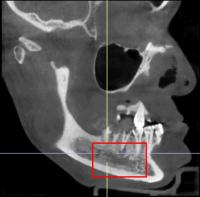

医生检查发现,王女士右侧下颌体部区域有明显包块,周围皮肤发红、肿胀,按压时有疼痛感。口腔内检查显示她存在多颗龋坏牙齿和残根,其中几颗叩击痛明显。拍摄的X光片进一步揭示了问题所在:她的下颌骨深处有一片不规则的“阴影区”,而且这个病灶离下颌骨里重要的神经血管非常近,若再拖延,可能会损伤神经,甚至导致面部变形。

结合临床表现和影像学检查,医生诊断王女士患有“下颌骨骨髓炎”—— 这是一种颌骨被细菌感染引发的炎症,就像骨骼被 “虫蛀” 一样,若不及时清除感染,炎症会持续破坏骨组织。病房医疗团队立即制定了综合治疗方案:首先进行抗感染治疗,控制炎症发展;随后进行手术清创,彻底刮除受感染的死骨组织。“考虑到王女士对外观的顾虑,我们特意选择从口内做切口,避免术后脸上留疤。”口腔颌面外科病房主任孙超解释说。